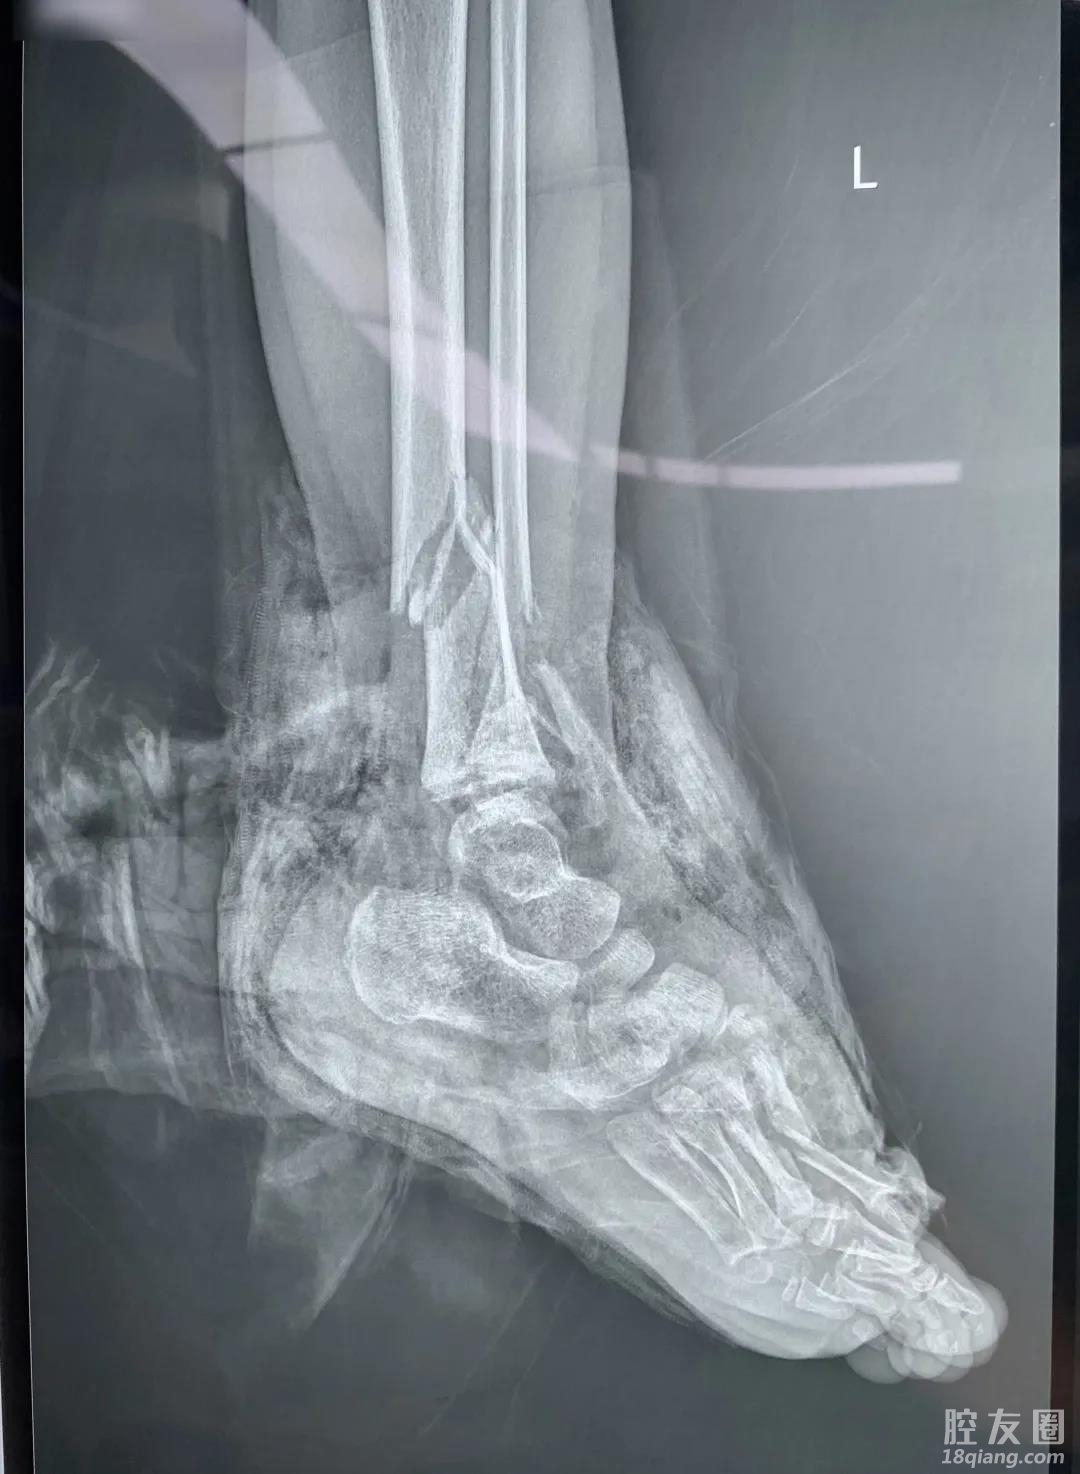

而小静的病情却不容乐观,她的左小腿和足背毁损严重,诊断为开放性骨折,踝关节脱位,肢体皮肤、血管、神经、肌肉、腱等组织重度损伤,伤口看上去令人触目惊心。

稠州医院迅速组织骨科、手外科等多名专家联合开展保肢手术,由于患者年纪小,伤势重,手术整整进行了8个多小时才顺利结束。